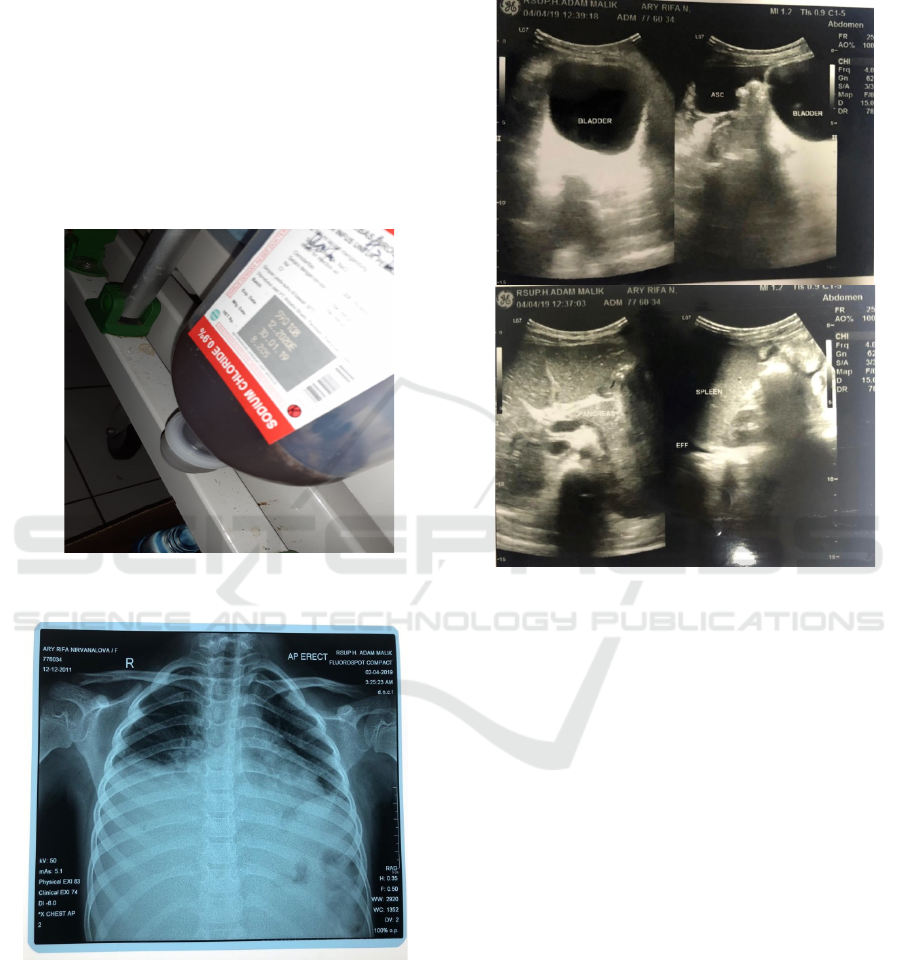

±500ml during follow up (figure 1).

From chest x-ray, we found bilateral pleural

effusion (figure 2). We did abdominal examination

in this patient and found ascites (figure 3).

Figure 1: Gastrointestinal bleeding

Figure 2: Chest X-ray showed bilateral pleural effusion.

Figure 3: Abdominal ultrasound revealed ascites.